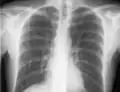

If a pneumothorax is suspected, an upright chest x-ray should be obtained. An upright chest x-ray is preferred because free air will migrate to the apex of the lung, where it is easily visualized. Of course, this is not always possible, particularly in critically ill patients in the intensive care unit. Radiographs obtained in the supine position fail to detect 25–50% of pneumothoraces.[6] Instead, bedside ultrasound is a superior method of detection in those too ill to obtain upright imaging.[3]

The line is then inserted using the Seldinger technique: a blunt guidewire is passed through the needle, then the needle is removed. A dilating device may be passed over the guidewire to expand the tract. Finally, the central line itself is then passed over the guidewire, which is then removed. All the lumens of the line are aspirated (to ensure that they are all positioned inside the vein) and flushed with either saline or heparin.[1] A chest X-ray may be performed afterwards to confirm that the line is positioned inside the superior vena cava and no pneumothorax was caused inadvertently. On anteroposterior X-rays, a catheter tip between 55 and 29 mm below the level of the carina is regarded as acceptable placement.[33] Electromagnetic tracking can be used to verify tip placement and provide guidance during insertion, obviating the need for the X-ray afterwards.

Chest x-ray with catheter in the right subclavian vein

The outline of superior vena cava on a chest X-ray is labeled at left.